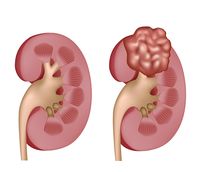

سرطان الكلى

| سرطان الكلى | ||

| معدل الانتشار | 208.500 عالمياً [14] | |

| معدل البقاء 5 سنوات | 73% (الولايات المتحدة) [10] | |

| حالات الوفاة | 13.570 (عالمياً، 2013) [15] | |

| عوامل الخطورة | خطر الإصابة عند الذكور ضعف ما عند النساء، وعند المدخنين ضعف ما عند غيرهم. يزداد خطر الإصابة ببعض أنواع المرض بسبب زيادة الوزن. معدلات الإصابة بسرطان الكلى أكبر عند العاملين بالأسبست والعاملين في أفران فحم الكوك. | |

| العلامات المنذرة | وجود دم في البول، ورم (كتلة) في منطقة الكلية، وَجَع كليل dull ache أو ألم pain في الجانب أو الظهر، أحيانا علامات أخرى مثل ارتفاع ضغط الدم أو شذوذ في عدد خلايا الدم الحمراء. | |

| الكشف والتشخيص | صور شعاعية للكلى، شاملة الحَقْن بالصبغة dyes؛ التصوير الطبقي التفرسي المحوسب (CT scans)؛ التصوير التفرسي بالرنين المغنطيسي (MRI scans)؛ تصوير الشرايين الشعاعي؛ الفحوص بالأمواج فوق الصوتية، وقد يُحتاج إلى الخزعة لتأكيد التشخيص.

| |

| العلاج | تتم بإزالة كامل الكلية المصابة أو جزء منها، وتكون عادة مع الغدة الكظرية المجاورة. ويمكن استخدام المعالجتين الشعاعية والانصمامية embolization ـ وهي إجراءٌ لسد الأوعية الدموية ـ للتخفيف من شدة الأعراض. تمّت الموافقة على استعمال الإنترليوكين وهو مادة لها دور في الجهاز المناعي، ولكنها تؤدي إلى تأثيرات جانبية سُمية خطيرة.

| ملاحظات | شهدت أمريكا الشمالية أعلى معدلات انشار سرطان الكلى، في حين كانت المعدلاات في آسيا وأفريقيا هي الأصغر.[16] | |